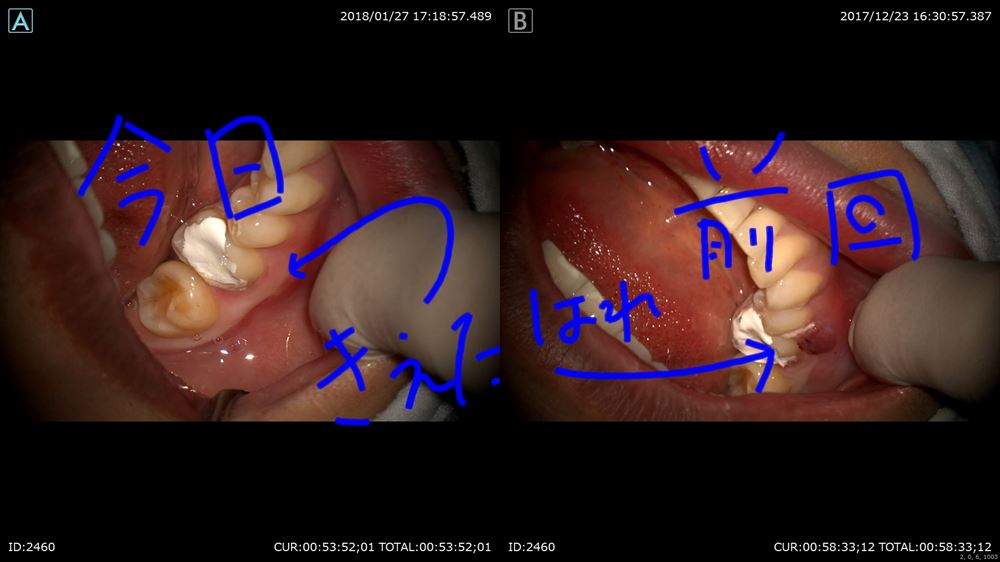

次のケースは解りやすいサイナストラクト

右が12月。こんなに右下6が腫れてる!!左は今日。治ってる!!!嬉しい!

これも丁寧な時間をかけた無痛治療の賜物です。